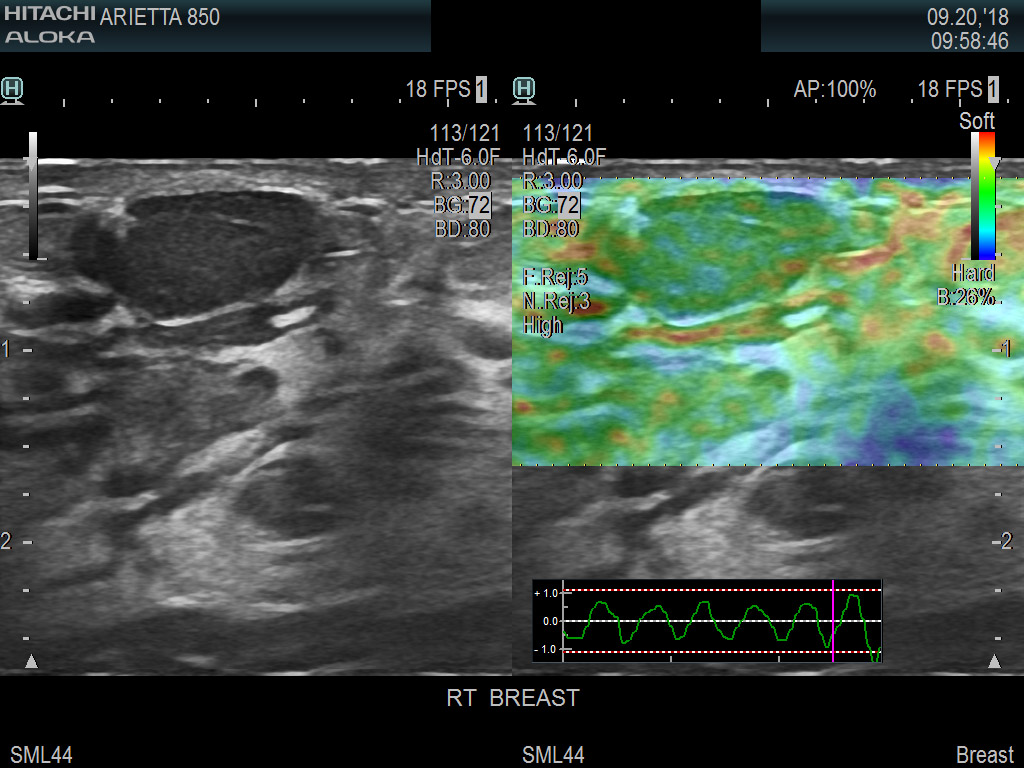

Superior guidance for all applications

Fujifilm Healthcare's dedication to Surgeons provides outstanding ultrasound technology, professional support and the specialized tools necessary to best perform comprehensive real-time ultrasound imaging in Breast Surgery, General Surgery, Laparoscopic Surgery, Neurosurgery, Robotic Surgery and Surgical Oncology.

Fujifilm Healthcare’s ARIETTA Precision features state-of-the-art digital architecture and advanced imaging technologies to redefine the capabilities of surgical ultrasound.

Imaging Clearly Defined

State-of-the-art digital architecture and advanced imaging features to redefine the capabilities of surgical ultrasound.